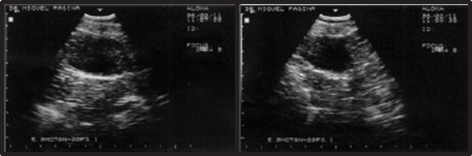

Figure 35 Ultrasonographic control at 3 months post-surgery.

Evolution

The patient has shown no significant clinical signs except for mild hematuria. Follow-up ultrasonography at 3 months (Figure 36) and 12 months post-cryosurgery showed no recurrence.

Figure 36 Ultrasonographic control at 12 months post-surgery.